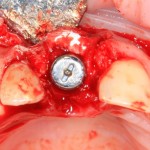

Немедленная имплантация — оптимальное решение в любой клинической ситуации